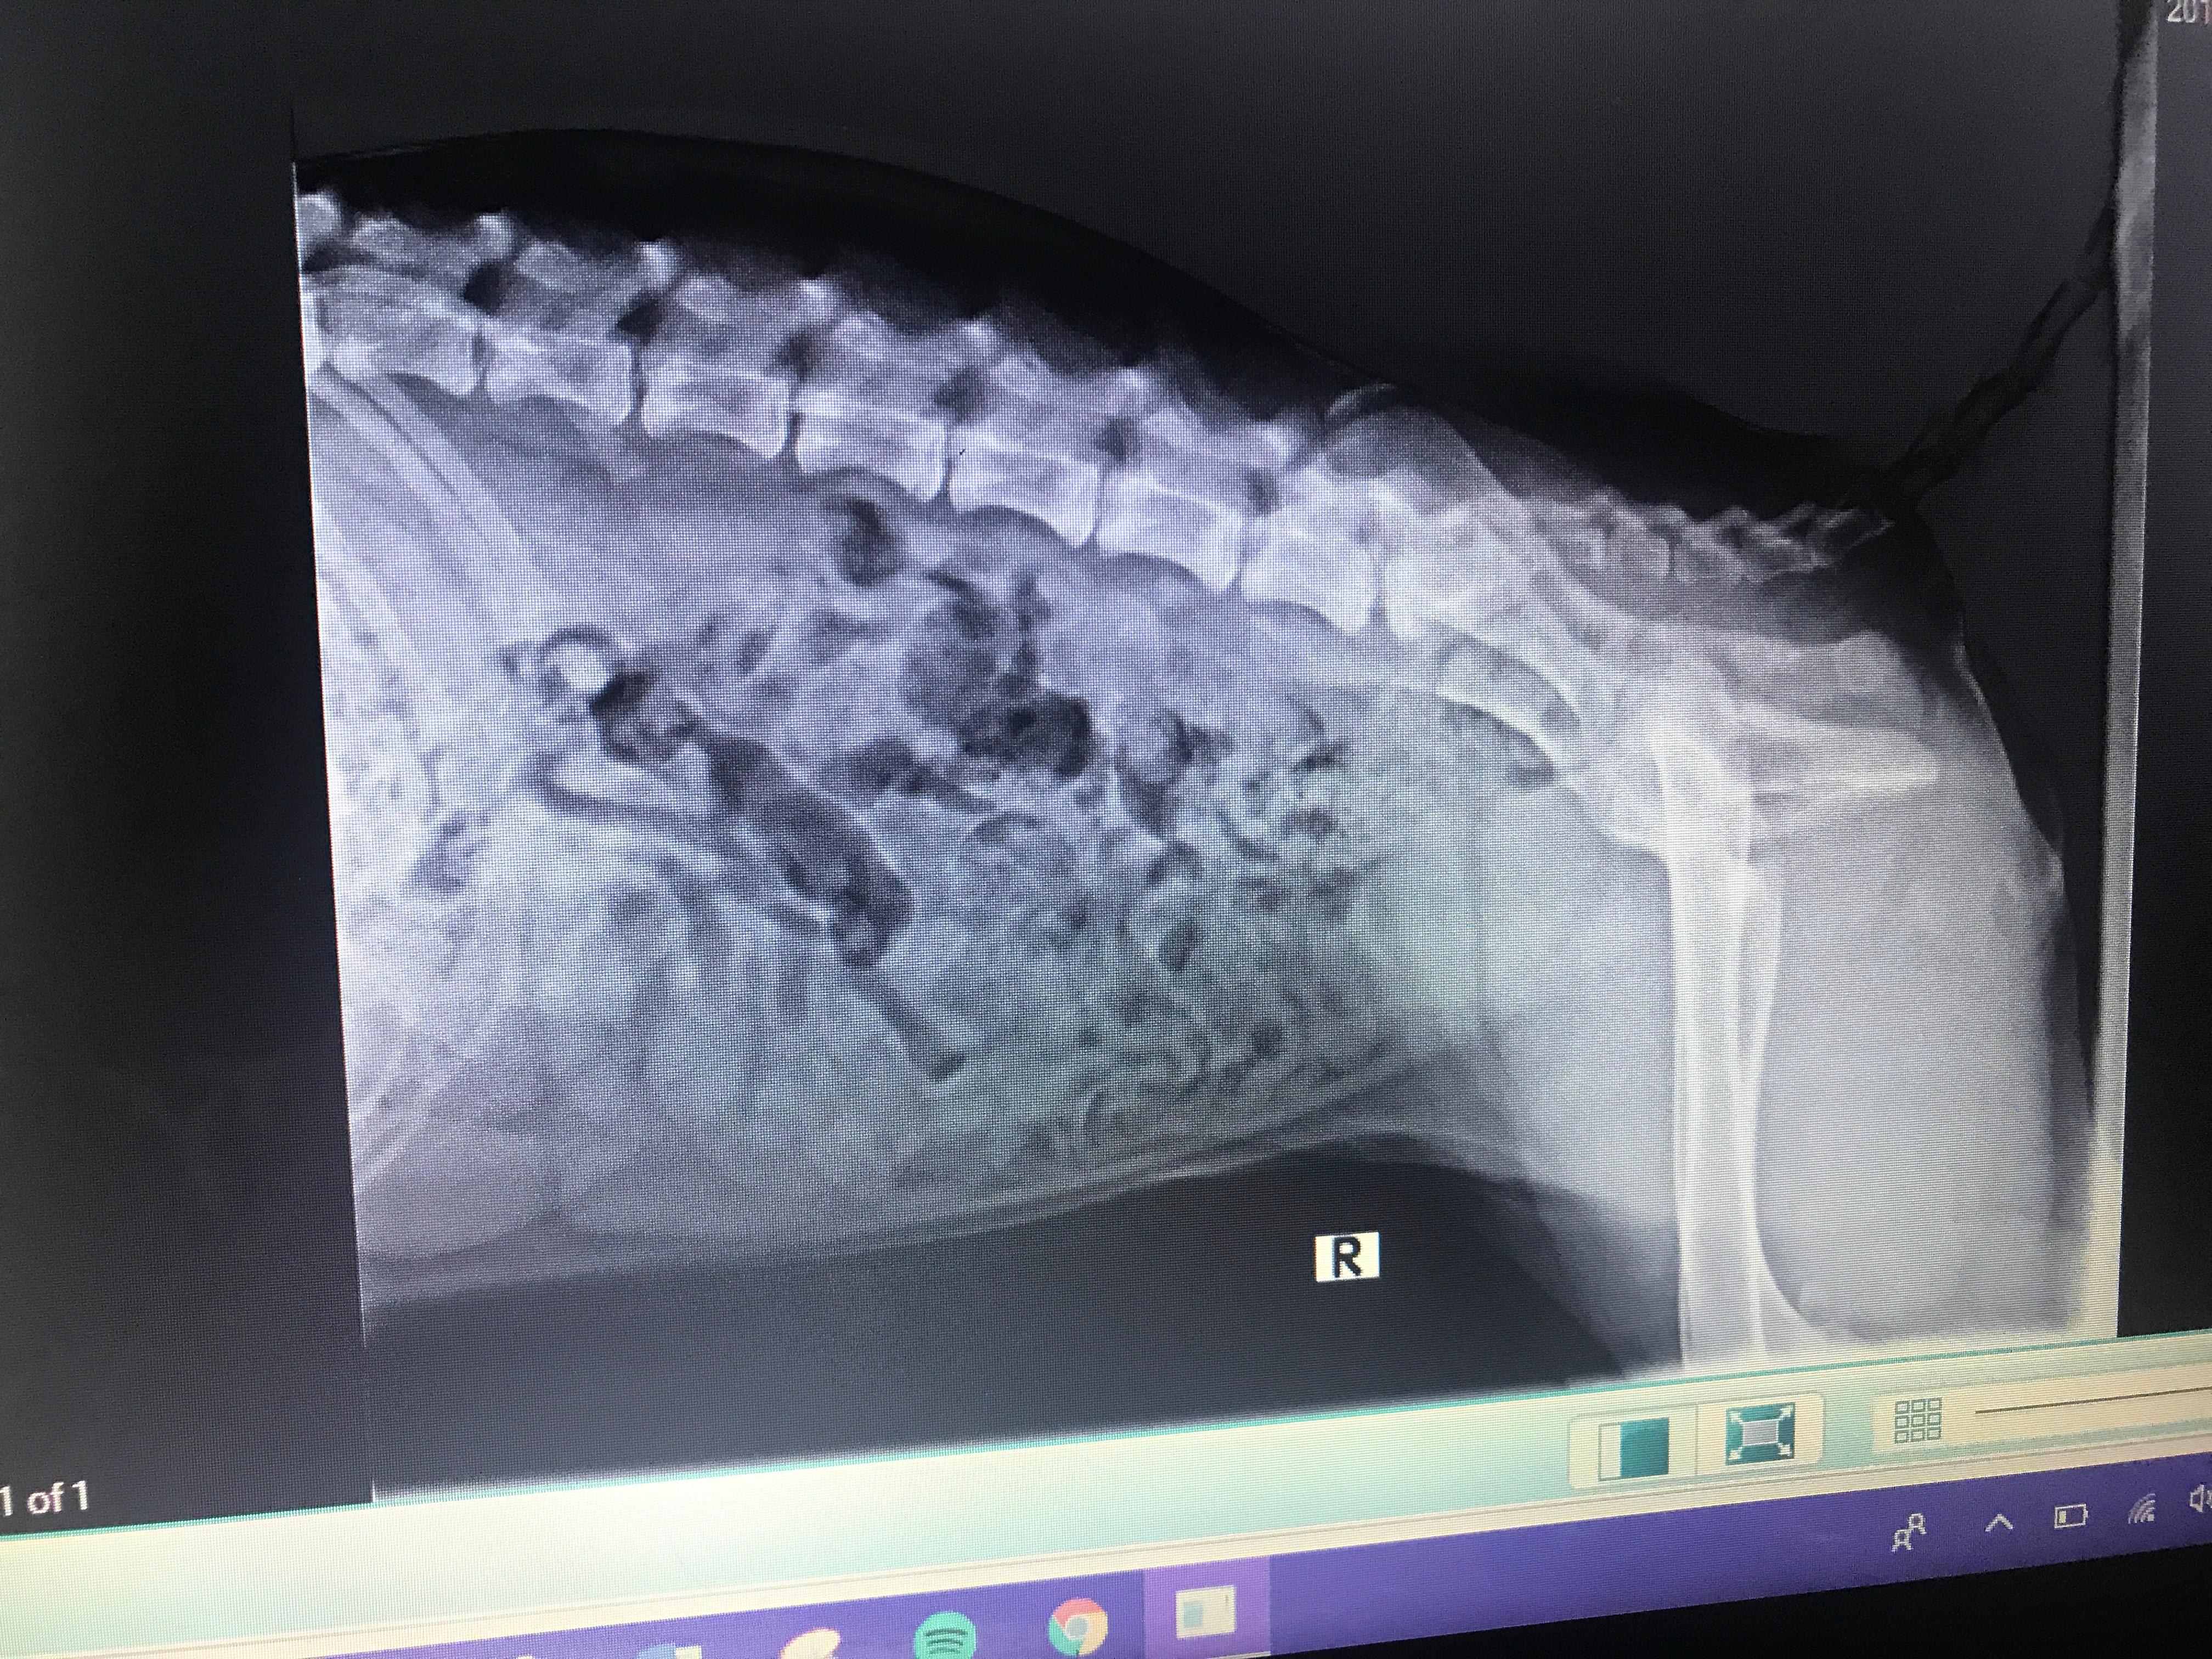

Pet's info: Dog | German Shepherd | Female | unspayed | 6 months and 2 days old | 41 lbs

I need a second opinion. Does my 6 month German Shepherd female have a hip problem? She has a hard time getting up and sometimes doesn’t want to walk

Bella can definitely have hip problems with her symptoms. With the X-rays provided it is not the most appropriate way to determine hip dysplasia. The best X-rays are sedated X-rays with the hind legs being extended straight and tilted slightly in. I would recommend when you spay her Bella you have them X-ray her hips at the same time to determine this. Once you have these X-rays if hip dysplasia is found, you can talk to a surgeon to find out what is the next step for Bella. Here is a link to a photo that shows you how the legs should be to evaluate hips. http://www.azpetscan.com/uploads/2/3/8/3/23831955/8701405.jpg?377 Thank you for using PetCoach.